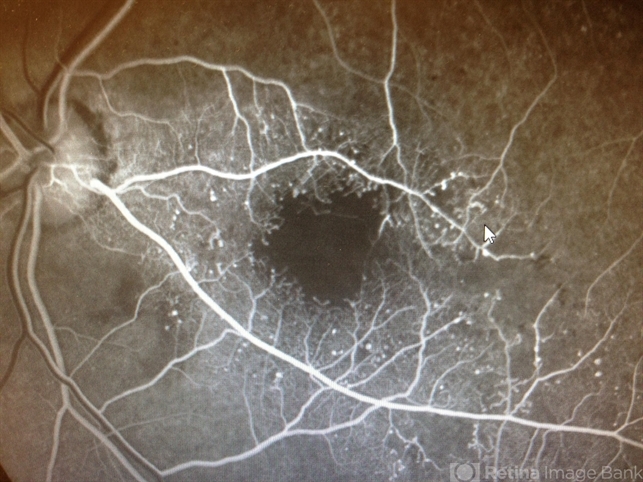

- Fluorescein angiogram of a 65-year-old poorly controlled diabetic with decreased vision in the left eye due to macular ischemia. HbA1C was 10. Vision was 20/80. Note the cilioretinal artery.